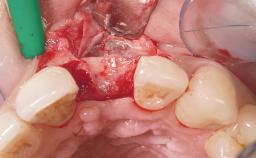

A 29-year-old female patient presented for treatment to replace the upper left central incisor tooth with an implant- supported restoration. The tooth had been intermittently symptomatic for the previous 12 months. The tooth had originally suffered trauma about 15 years previously. Several endodontic treatments had been performed, including an apicectomy procedure to retain the tooth. The patient was healthy and a non-smoker. She had reasonable expectations in regard to esthetic outcomes and the risk of marginal tissue recession following treatment. At medium smile, the gingival margins of the upper teeth were visible, with a display of 3 to 4 mm of the gingival margins. Gingival recession of tooth 21 and a discrepancy in the gingival levels between teeth 11 and 21 was observable during normal speech and smile.

| Placement Protocol | Immediate implant placement |

| Tooth Site | Maxillary incisor or canine |

| Socket Morphology | Single-root socket |

| Socket Integrity | Damage to one or more bone walls |